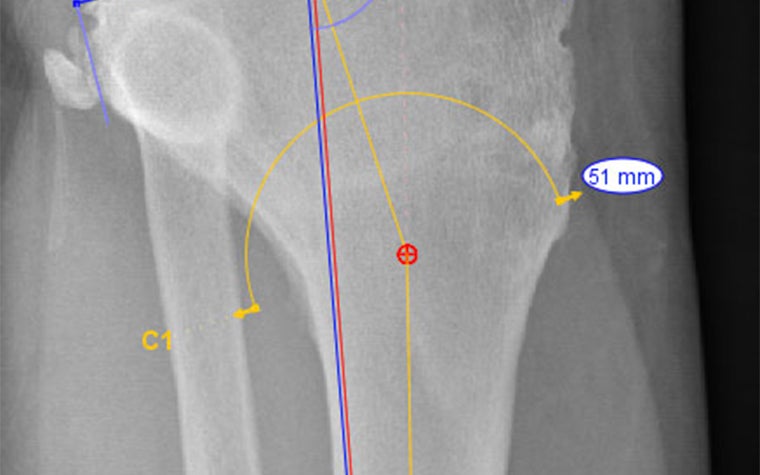

Considering the right leg first, examination of the long-leg weight-bearing AP X-ray shows good mechanical axis alignment but a significantly oblique knee joint line (figure 1). It was apparent that mild osteoarthritis had become worse over time, presumably as a result of the joint obliquity.

This confirmed that the knee joint line convergence angle was outside of normal range. Specifically, using the nomenclature developed by Paley et al., the mLDFA (mechanical Lateral Distal Femoral Angle) and MPTA (Medial Proximal Tibial Angle) were 7.5 degrees and 10 degrees outside of normal range, respectively.